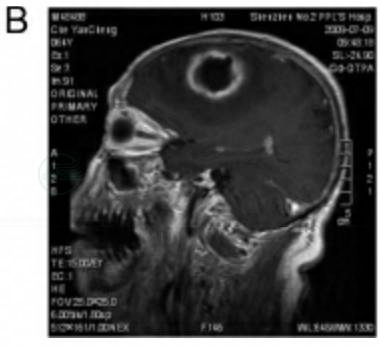

病例B

患者裴某,男性,47岁。

主诉:反复发作性右侧肢体麻木1月余。

现病史:患者自1月余前出现多次发作性右侧肢体麻木,每次持续3~5分钟,可自行缓解,无其他伴随症状。自诉有中耳炎病史。1个月前有发热史。头颅CT见左额顶囊性占位,周围大面积水肿。

体格检查:言语模糊,右侧肌力略较左侧下降,余正常。

诊疗经过:入院后行MRI检查见左额占位病变,中间囊性坏死,有分隔,可见不均匀增强,瘤周大面积水肿。考虑胶质瘤Ⅱ~Ⅲ级(图3)。胸片、腹部B超结果未见明显异常。术前病例讨论:考虑恶性胶质瘤,不除外脑脓肿。入院后4天行手术,术中见肿瘤呈胶冻样,伴有坏死,术中冰冻为胶质瘤Ⅲ级,予切除肿瘤。

术后病理:胶质母细胞瘤,部分为小胶质母细胞(图4)。

图3